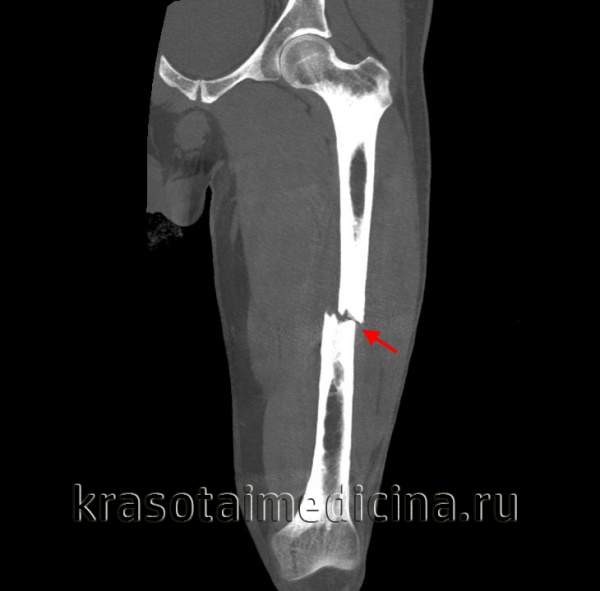

Диафизарный перелом бедра – тяжелая травма, сопровождающаяся болевым шоком и значительной кровопотерей.

Пациент с переломом бедра предъявляет жалобы на сильную боль в месте повреждения. В области перелома наблюдается отечность, кровоизлияние, деформация конечности и патологическая подвижность. Нога, как правило, укорочена. Перелом бедра может сопровождаться повреждением нерва или крупного сосуда. Возможно развитие травматического шока, обусловленного резкой болью и выраженной кровопотерей.

При переломе бедра существует опасность развития травматического шока. Профилактические противошоковые мероприятия включают в себя адекватное обезболивание, блокаду места перелома. При значительной кровопотере проводится переливание крови и кровезаменителей. Гипсовая повязка на начальном этапе лечения не применяется, поскольку с ее помощью невозможно удержать отломки в правильном положении. В качестве основных методов лечения используется скелетное вытяжение, аппараты внешней фиксации и операция (остеосинтез).

Груз может быть увеличен у молодых пациентов с хорошо развитыми мышцами. Средняя величина груза в начале лечения – около 10 кг. По мере устранения смещения груз уменьшают. После снятия вытяжения на поврежденную конечность накладывают гипсовую повязку на срок до 4 месяцев. При консервативном лечении коленный и тазобедренный сустав долгое время остаются неподвижными. Оперативное лечение позволяет увеличить подвижность пациента и предупредить развитие контрактур. Операцию проводят после нормализации состояния больного. Остеосинтез выполняют, используя пластины, штифты и стержни.